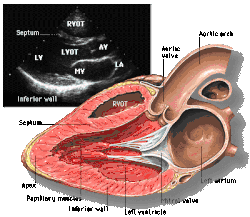

Parasternal long axis (PLAX)

This view is obtained to the left of the sternum and views the heart in its long axis. In this view, the mitral valve, aortic valve, right ventricular outflow tract, base of the left ventricle, and the left atrium can be visible. Angulation in this view can bring the right ventricular inflow tract and tricuspid valve into view, and angulation the opposite way can bring the pulmonary valve into view.

In this view, it is possible to appreciate the long-axis cross section of the mitral and aortic valves. The classic "hockey stick" shape of rheumatic mitral stenosis can be appreciated in this view. However, the angle of the probe with these valves can lead to under-appreciation of valve dysfunction.

The parasternal long view of the pulmonary valve is the only view of the posterior leaflet.

Structures visible:

- Anterior septal and inferior lateral walls of the left ventricle

- Left atrium

- Mitral valve in long-axis with chordae

- Aortic valve in long-axis

- Tricuspid valve in long-axis (angulated) and right ventricular inflow tract

- Pulmonary valve in long-axis (angulated) and right ventricular outflow tract